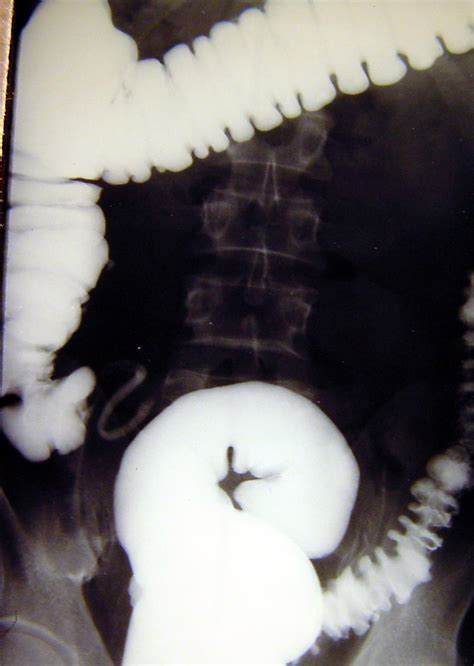

Diverticulitis occurs when small pouches (diverticula) in the colon wall become inflamed or infected. While initial treatment focuses on gut rest and medication, chronic or complicated cases shift the focus toward permanent solutions. Doctors typically evaluate the necessity of surgery for diverticulitis based on the frequency, severity, and complexity of the disease. You might be a candidate for surgical intervention if you experience the following: